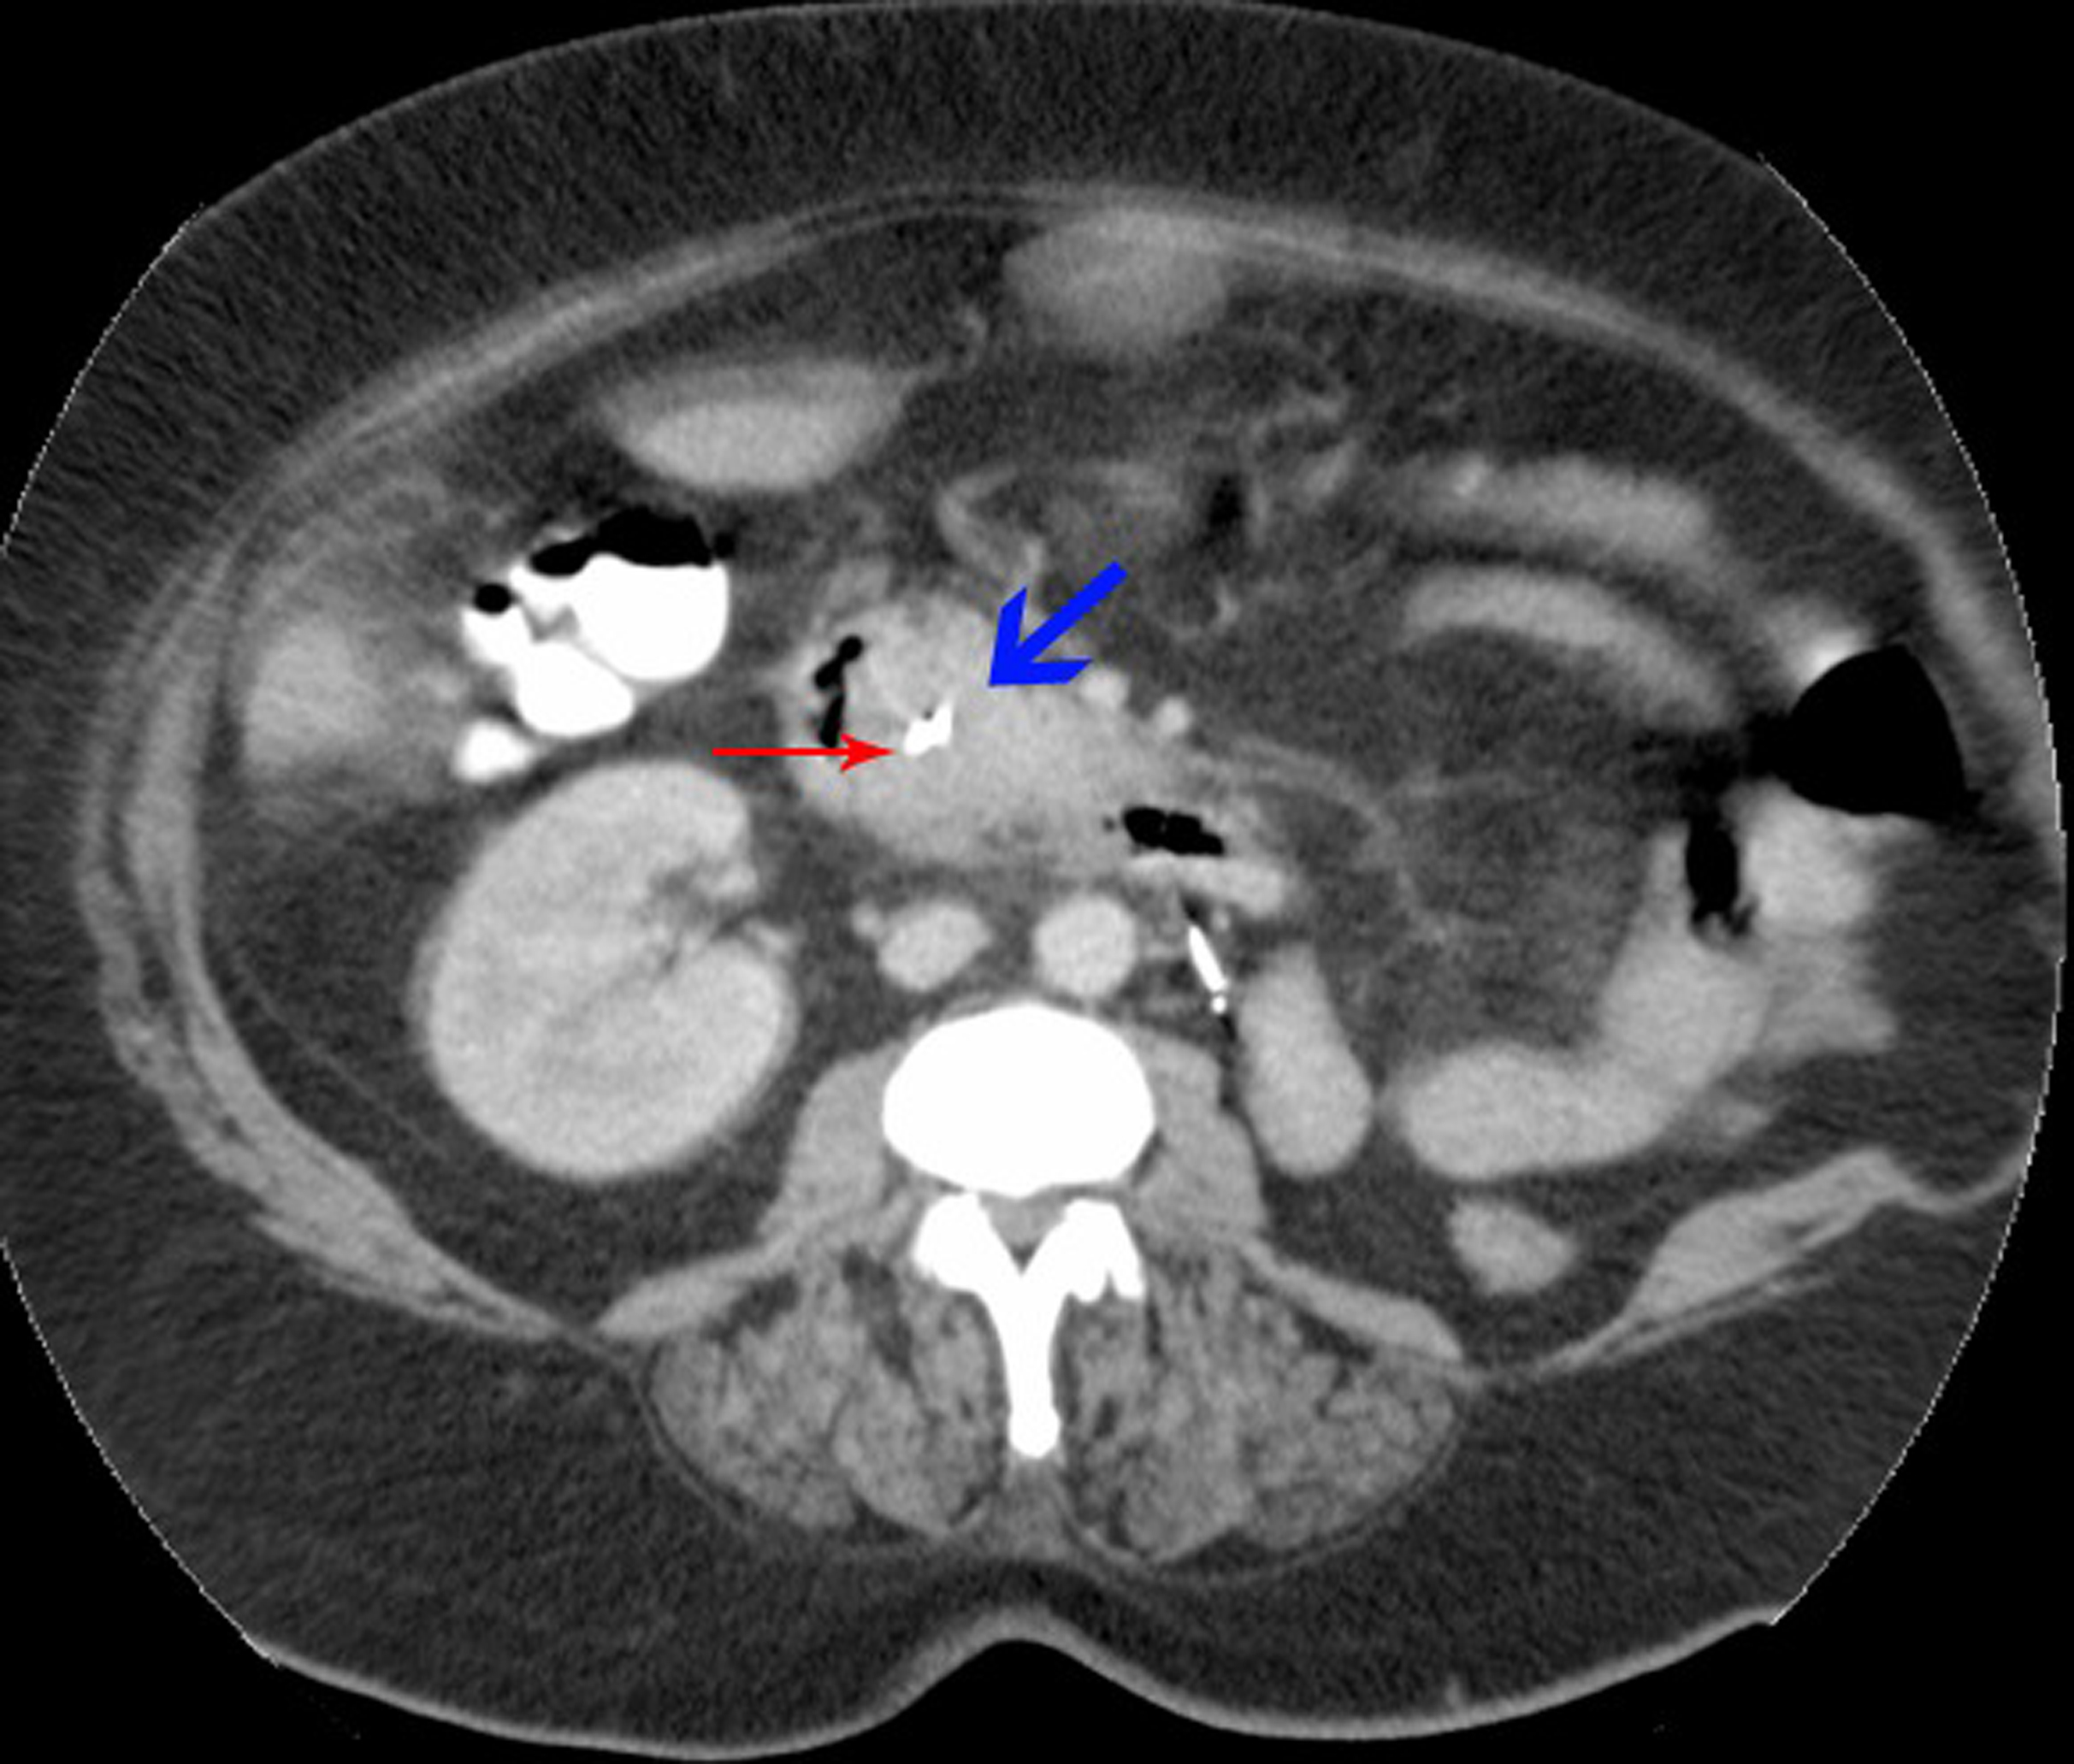

A biliary stent was inserted successfully during the endoscopic retrograde cholangiopancreaticogram (ERCP) (Fig. 2) and satisfactory drainage was achieved. Her liver enzymes and bilirubin improved significantly. A restaging CT showed a 6.0 x 4.5 cm mass involving the uncinate process of the pancreas and second part of the duodenum (Fig. 3, 4). New liver lesions were also seen.

![]() Click for large image | Figure 3. Cross-section of CT abdomen: blue arrow - tumor deposit; red arrow - biliary stent, D2 of duodenum to the right. |